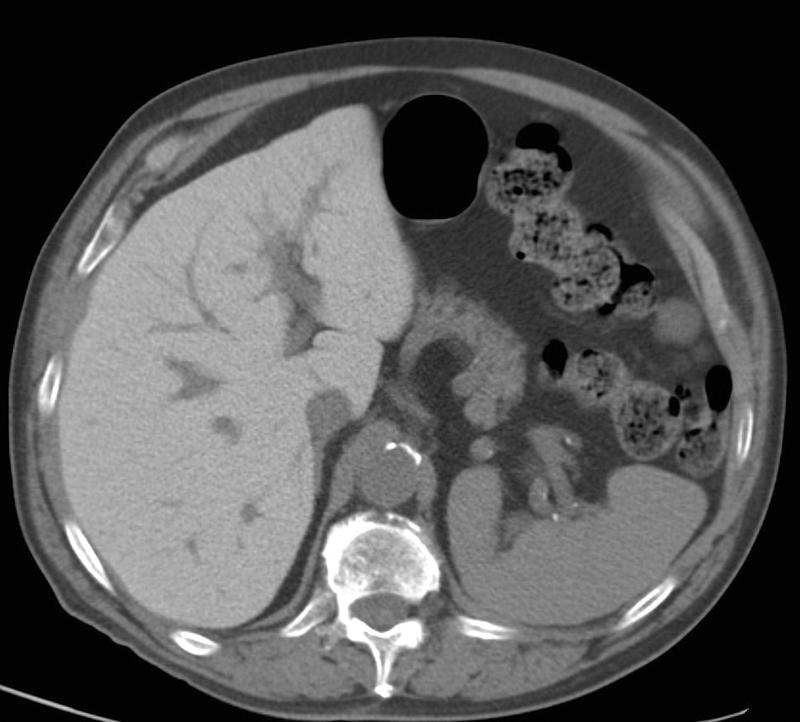

Amiodarone liver